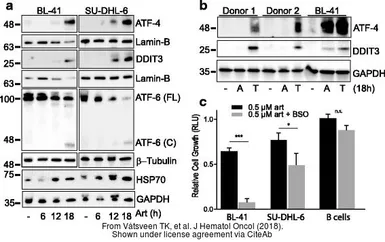

The data was published in the journal J Hematol Oncol in 2019. PMID: 31324208